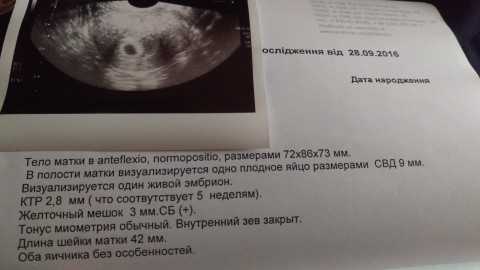

УЗИ двухплодной беременности на 5 неделе: Подборка изображений

Раздел: Калейдоскоп образов